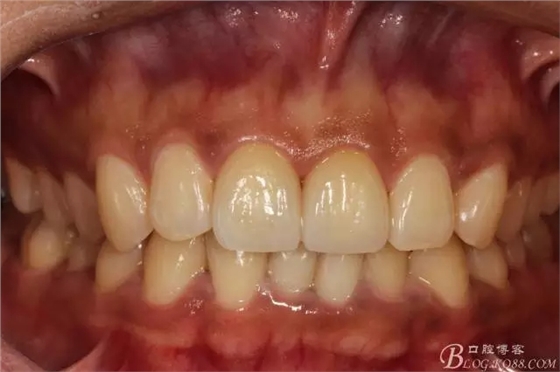

半年后(2016.9)復(fù)查照(這次復(fù)查已完全適應(yīng)修復(fù)后的效果,冷熱也不敏感了,我的心也就放下了)